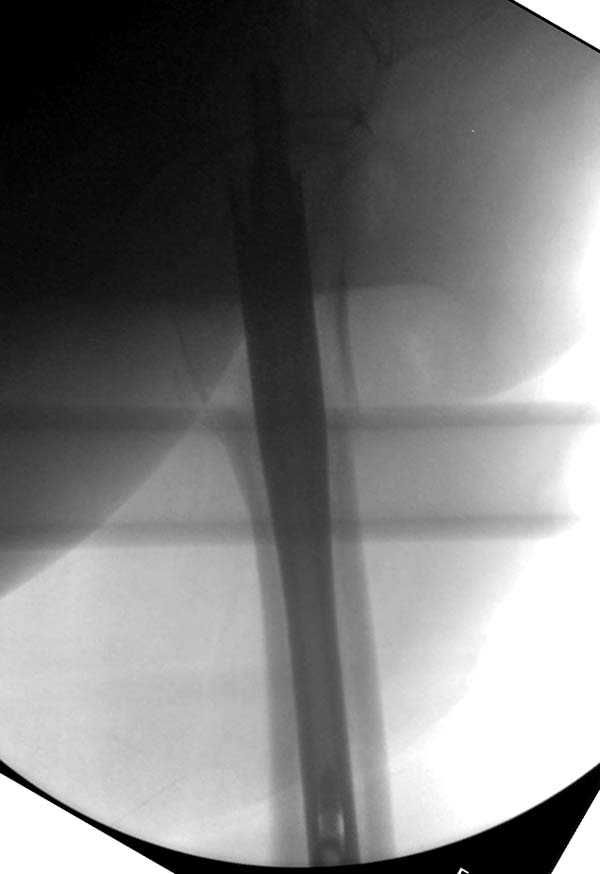

Здесь представлен случай, где в послеоперационном периоде обнаружена техническая ошибка, Gamma 3 установлен с нарушением методики. Больная в 91 лет, прооперирована через день после поступления и выписана через 48 часов.<br>

При первом послеоперационном поликлиническом осмотре больная предъявила жалобы на боли в бедре. В серийных снимках обнаружен продольный перелом верхнего отдела бедра.<br>

Считаем, что техническая ошибка произошла во время установки гвоздя, когда рассверливанию канала не уделили должного внимания. Канал остался узковат, и гвоздь был забит с силой.